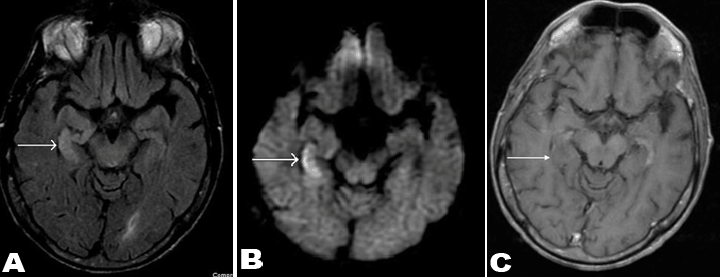

A 56-year-old male with recently diagnosed rectal cancer presented in the emergency department with recurrent seizures and disorientation for some days. Magnetic resonance imaging scan of brain demonstrated hyperintense signal on T2- FLAIR image (Figure 1A) and restricted diffusion on diffusion weighted image (Figure 1B) in right medial temporal lobe. There was no enhancement after contrast administration (Figure 1C). Patient's initial computed tomography (CT) scan of the abdomen and pelvis (Figure 2A-B), and positron emission tomography (PET) scan (Figure 2C) showed the presence of a large rectal mass with intense metabolic uptake. Based on clinical history and imaging findings, diagnosis of PLE was suggested. Serologic investigation showed a highly positive titer for anti-Ri (1:2560, normal <80). Subsequent cerebrospinal fluid analysis also showed increased titers of anti-Ri antibody with no findings to suggest viral or bacterial encephalitis. Since patient was already on chemotherapy treatment for rectal cancer, antiepileptic therapy and steroid treatment were also started. In next few days, the patient was free from seizure episodes and the neurological symptoms gradually improved. Follow-up MRI scan of brain was showed complete interval resolution of the abnormalities (Figure 3A-C).

Figure 3: (A) Axial T2-FLAIR, (B) Diffusion weighted, and (C) Contrast enhanced axial T1-weighted images showing complete resolution of previously seen abnormal signal in right medial temporal lobe with no contrast enhancement.